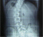

La máxima seguridad, la mejor tecnología y un equipo multidisciplinario centrado en ofrecer la mejor atención a nuestros pacientes. Esa es la estructura que distingue al Centro de Columna de Clínica Las Condes.

La atención de problemas de columna desde lo más simple a lo más complejo recibirá la mejor atención para la máxima recuperación en nuestro Centro de Columna.